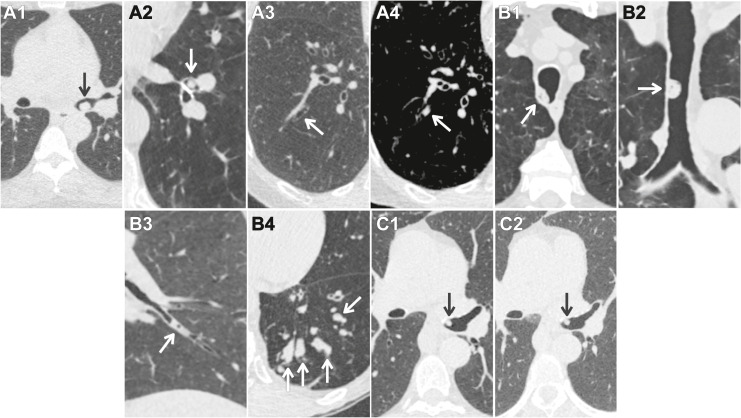

Hình 7. Nốt đường thở. (A) Các nốt đường thở theo Lung-RADS v2022 được phân loại dựa trên vị trí, hình thái, số lượng, và thời gian tồn tại. Các nốt đường thở mới ở phân thùy hoặc gần trung tâm hơn và không có các đặc điểm lành tính được phân loại Lung-RADS 4A với khuyến cáo chụp CT liều thấp (LDCT) 3 tháng sau để đánh giá khả năng giải quyết (A1: nốt thân phế quản gốc trái [mũi tên], A2: nốt phế quản thùy dưới trái [mũi tên]). Các nốt đường thở phân thùy được phân loại là Lung-RADS 2 (A3: sàng lọc ung thư phổi [LCS] thời điểm ban đầu với đường thở phân thùy thông thoáng [mũi tên], A4: CT LCS hàng năm với nốt đường thở phân thùy mới [mũi tên]). (B) Sự hiện diện của khí bên trong nốt đường thở, đặc biệt là khi không có thành phần mô mềm, với đậm độ trung bình < 21 đơn vị Hounsfield thiên về tiết dịch (B1, B2, B3 [mũi tên]). Mờ nhiều ống đường thở thiên về nút nhầy (B4, mũi tên). Những dấu hiệu này có thể được phân loại là Lung-RADS 2. (C) Một bệnh nhân 70 tuổi có một nốt mô mềm ở phế quản gốc trái trên LCS hàng năm (C1, mũi tên) được phân loại là Lung-RADS 4A và ổn định trên LDCT 3 tháng (C2, mũi tên). Các nốt đường thở vẫn tồn tại khi theo dõi vẫn đáng ngờ và được nâng lên Lung-RADS 4B với khuyến cáo đánh giá chẩn đoán, thường là giới thiệu đánh giá lâm sàng và nội soi phế quản.